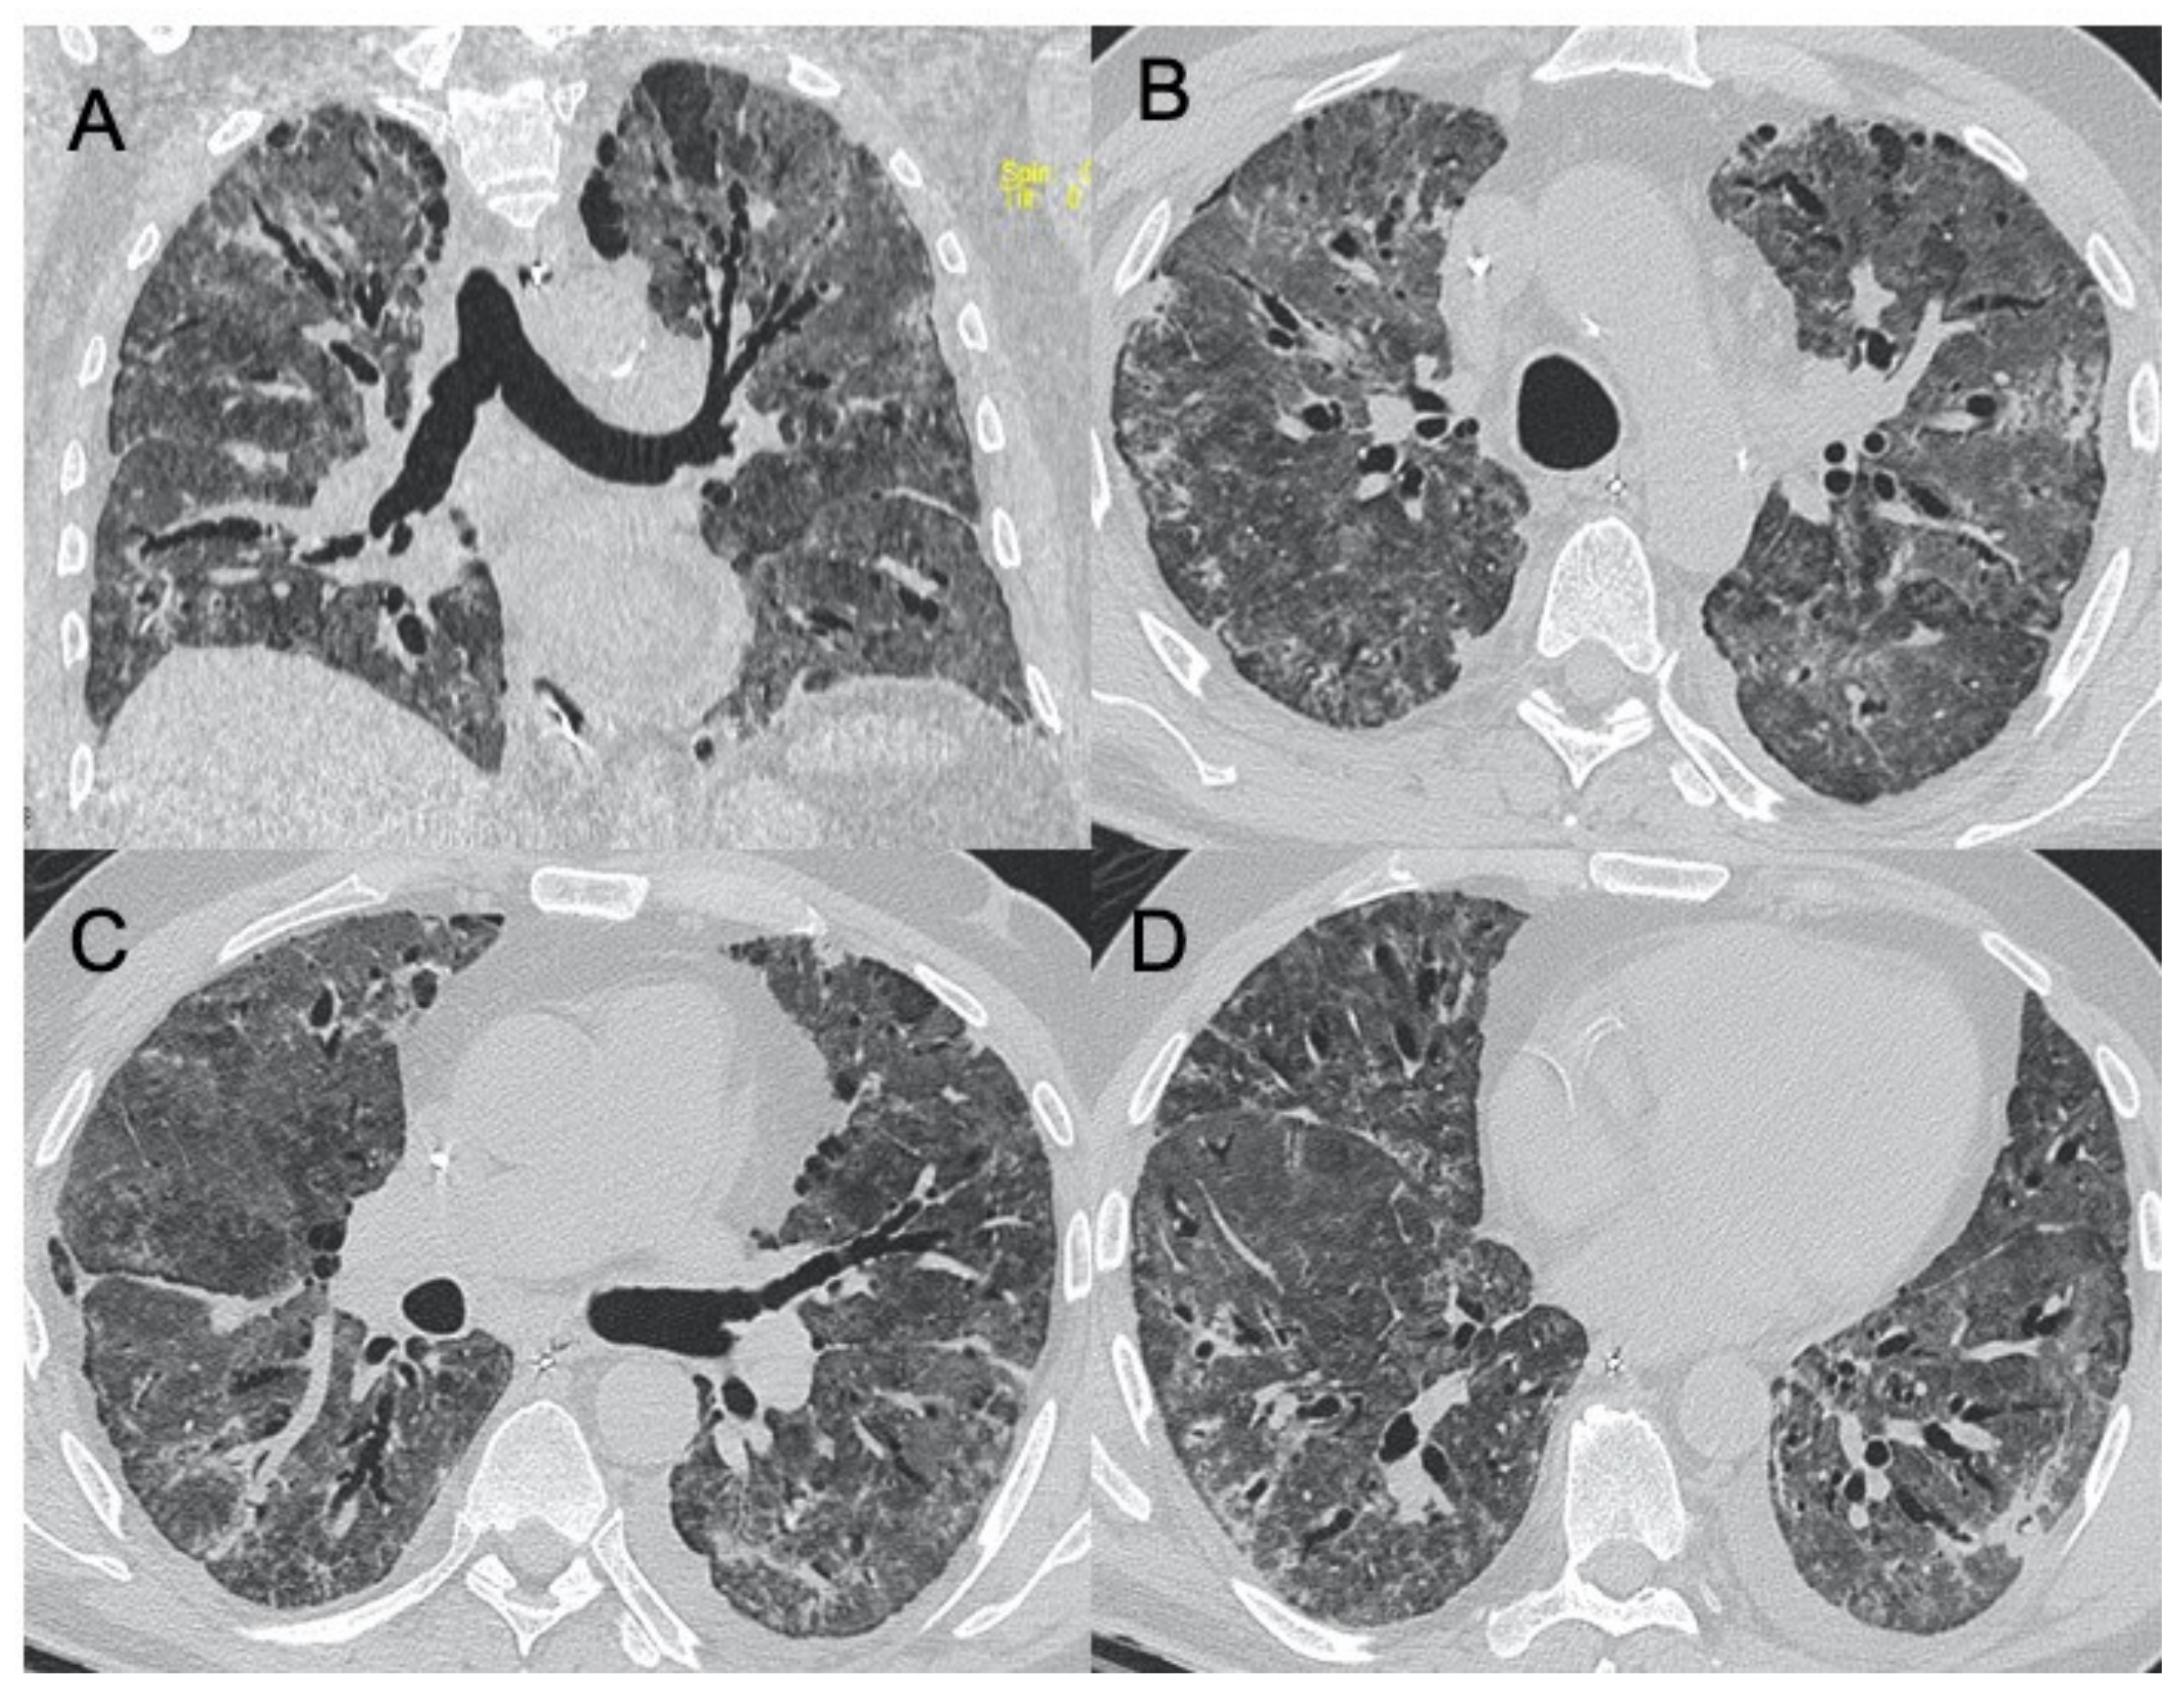

| Herpes virus | Bilateral areas of consolidation with GGO with lobular, segmental, or sub-segmental distribution | Multifocal areas of segmental or sub-segmental GGO are observed; pleural effusion is frequent | Figure 6 |

| Varicella Zoster | Multiple nodules (5–10 mm) with defined margins that may tend to confluence. Pleural effusion and lymphadenopathy may be present although they are not common | Well-defined nodules (1–10 mm) with a halo of GGO. These millimetric lesions may calcify. | Figure 7 |